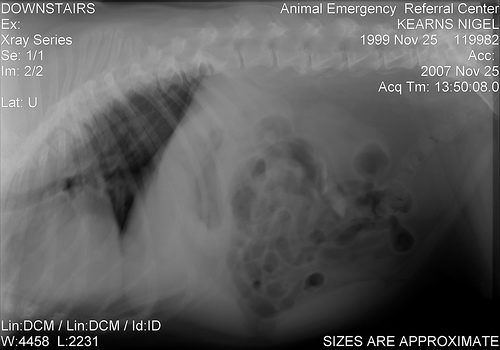

犬で多いのが僧帽弁閉鎖不全症、猫で多いのが肥大型心筋症という病気になりますが、この2つの病気はともに進行がすすむと、1か月に1回はエコーの検査やレントゲンの検査を行い、薬の量を検討する必要があります。

現在、往診でも可能なポータブルのエコー検査機器もありますが、解像度は非常に低く、心臓の様に常に動いている臓器の検査はほとんどできません。

実際に今でも通常の動物病院で診察をしているので、レントゲンやエコー検査のありがたみは日にしみて感じていますし、外科手術が必要な犬や猫には外科手術を積極的に行っています。